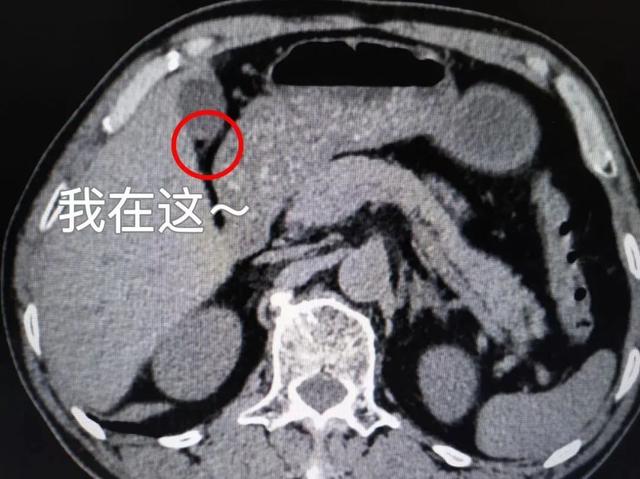

胆囊阳性结石就是等密度胆固醇结石(ct上表现与胆汁密度一致)或低密度